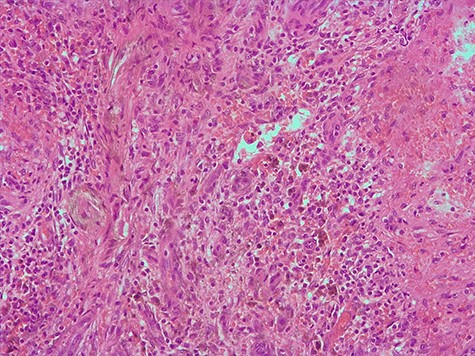

Histopathology examination confirmed the presence of areas of sclerosis, with scarring tissue surrounded by abundant vascular spaces (Fig. 4). The immunohistochemical evaluation revealed clusters of differentiation CD31+, CD34+ and CD8—cells consistent with SANT (Fig. 5).

Hematoxylin and eosin 200X, area of the biggest lesion composed mainly by abundant capillaries.